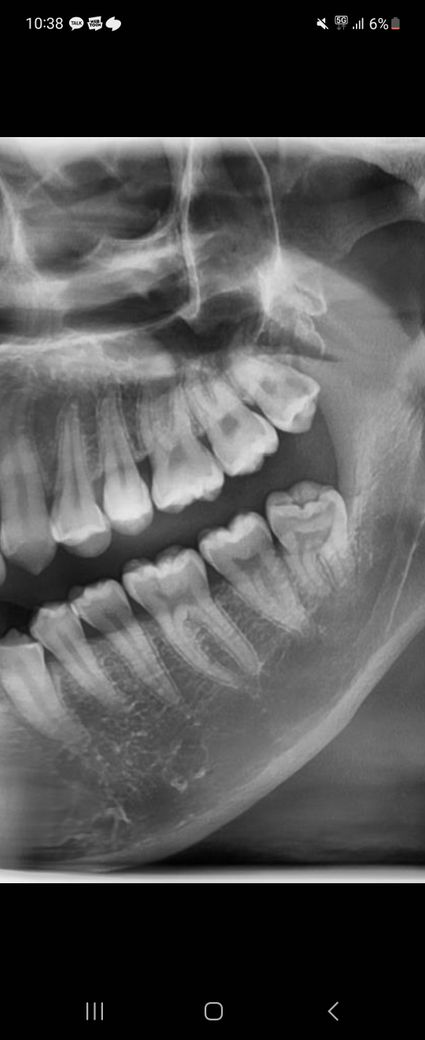

오른쪽 위사랑니 충치가 많이 심한가요

위쪽 사랑니 충치가 많이 심한가요? 뿌리염증 있는지 궁금합니다.

1. 해당부위는 왼쪽위 사랑니입니다

2. 옆면 뒤쪽 검은부분이 방사선사진 상 충치로 의심됩니다

3. 일반치아였다면 충치치료 진행하고 신경까지 근접하였으므로 보호막을 형성하거나 충치 제거과정 중 신경이 노출되면 신경치료 들어갈 수도 있습니다

사진으로만 봤을 경우에는 치아 안쪽의 음영이 넓은것으로 봐서 충치가 심하다고 생각이 됩니다.

왼쪽위 사랑니는 많이 썩은거 같습니다. 일반치아라면 신경치료 또는 발치가능성도 잇을만큼 충치가 심합니다.

상아질까지 우식이 깊게 진행된 상태이며 치료를 해봐야 알겠지만 신경치료 가능성이 높습니다.